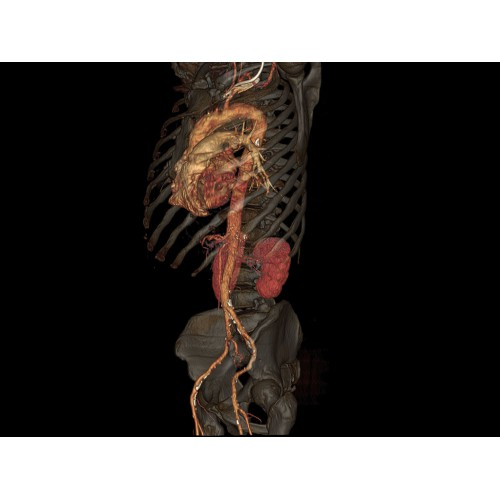

Кардиология

• Неинвазивная оценка состояния коронарных артерий.

• Диагностика атеросклероза и других сердечно-сосудистых патологий.

Онкология

• Раннее выявление новообразований и контроль эффективности лечения.

• Планирование лучевой терапии с высокой точностью.